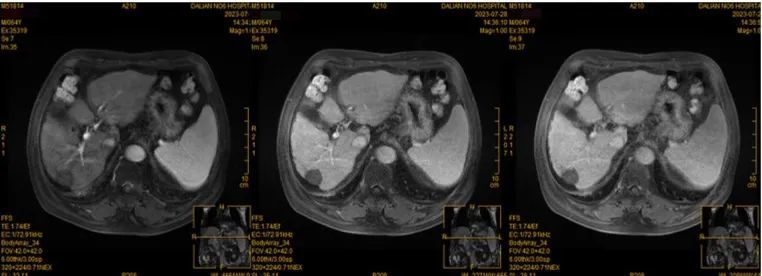

术后MRI检查(2023.07.28)

肝右叶后上段见一术后病灶,直径约2.0cm,增强扫描病灶及灶周未见确切异常强化;

肝右叶后上段小肝癌介入术后,未见确切异常血供。